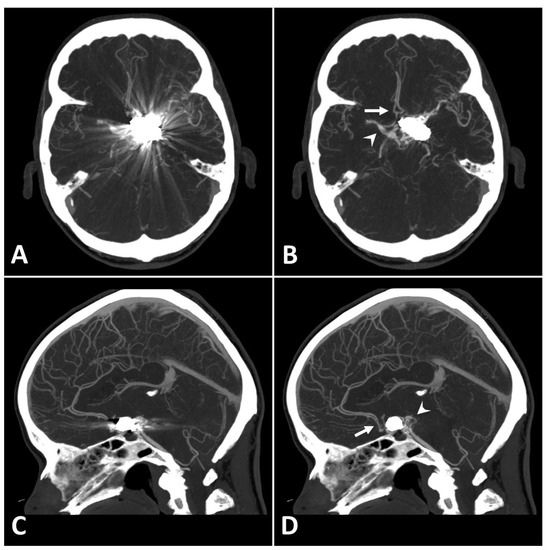

Metal artifact index (MAI) (which was considered to be the mean image noise) was significantly reduced in SEMAR images compared to standard images in close vicinity to (70.9 ± 22.1 vs. 331.8 ± 157.5, respectively) and more distant from the coil package (24.7 ± 6.7 vs. 52.4 ± 20.3, respectively; p < 0.001 each). Figure 2 and Figure 3 demonstrate significantly improved image quality and visualization of arteries after applying the SEMAR algorithm on images with coil-artifacts.

Figure 3.

Exemplary follow up UHR-CT-angiography in axial and coronal plane without (A,C) and with SEMAR (B,D) of a 48-year-old female after intracranial coil-embolization of a left sided middle cerebral artery aneurysm, demonstrate the efficacy of SEMAR in visualizing vessels adjacent to the coil package like the ipsilateral middle cerebral artery (thick arrow in (B)), the anterior cerebral artery (thin arrow in (B)), the ipsilateral posterior cerebral artery (arrowhead in (B)), and the middle cerebral artery (thick arrow in (D)). All images were reconstructed as MIP (Maximum Intensity Projection) with 12.5 mm slice thickness.